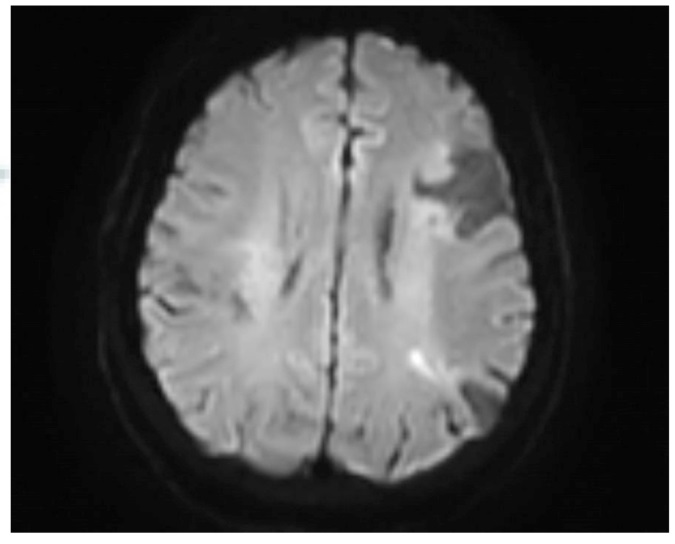

Ishikawa M, Nakayama K, Ishibashi T, et al. Case series of cerebral infarction with trousseau's syndrome associated with malignant gynecological tumors[J]. Mol Clin Oncol, 2016, 5(1): 138-142. DOI: 10.3892/mco.2016.888.